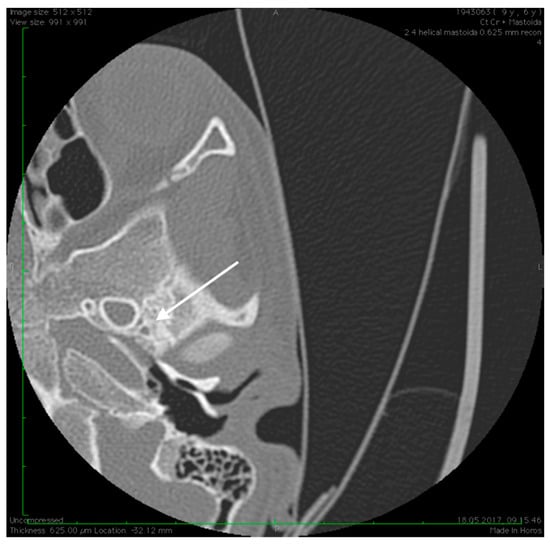

Figure 4.

High resolution axial CT scan of right temporal bone exposing the unusual wide facial canal and the missing oval window on the right side (arrow).

Preoperative CT imaging of middle ear surgery patients is mandatory and careful interpretation of the results can sometimes prevent accidental injuries brought to a PSA. The usual findings are a small, abnormal, canaliculus leaving the carotid canal or the facial nerve, a straight line structure crossing over the promontory, an unusual widening of the fallopian canal or a different canal parallel to it between the geniculate and the oval window niche and absence of the foramen spinosum []. Our CT findings coincide with some of the aforementioned signs, as there can be seen no trace of the foramen spinosum in the affected ear (Figure 5), in contrast to the contralateral ear (Figure 3). There is also a widening of the facial nerve canal that can be observed in Figure 4. It came as no surprise that the stapes could not be described in the CT images, as the literature review acknowledges the possible stapes malformations that come along with PSA.